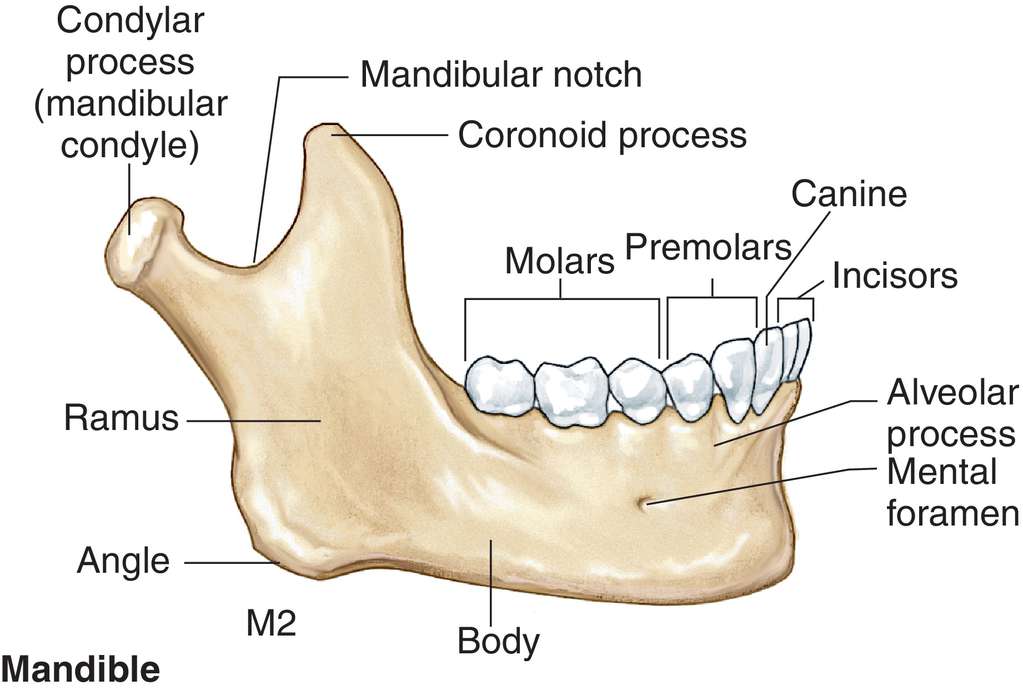

Discover the sophistication of annotated illustration of the jaw's anatomy | stable diffusion online with our curated gallery of numerous images. featuring elegant examples of photography, images, and pictures. ideal for luxury lifestyle publications. Browse our premium annotated illustration of the jaw's anatomy | stable diffusion online gallery featuring professionally curated photographs. Suitable for various applications including web design, social media, personal projects, and digital content creation All annotated illustration of the jaw's anatomy | stable diffusion online images are available in high resolution with professional-grade quality, optimized for both digital and print applications, and include comprehensive metadata for easy organization and usage. Our annotated illustration of the jaw's anatomy | stable diffusion online gallery offers diverse visual resources to bring your ideas to life. Professional licensing options accommodate both commercial and educational usage requirements. Cost-effective licensing makes professional annotated illustration of the jaw's anatomy | stable diffusion online photography accessible to all budgets. Regular updates keep the annotated illustration of the jaw's anatomy | stable diffusion online collection current with contemporary trends and styles. Multiple resolution options ensure optimal performance across different platforms and applications. Time-saving browsing features help users locate ideal annotated illustration of the jaw's anatomy | stable diffusion online images quickly. Whether for commercial projects or personal use, our annotated illustration of the jaw's anatomy | stable diffusion online collection delivers consistent excellence.

![[DIAGRAM] Blank Diagram Of Human Skull - MYDIAGRAM.ONLINE](https://fc05.deviantart.net/fs71/i/2012/270/0/0/annotated_human_skull_anatomy___side_view_by_shevans-d5g1lgl.png)